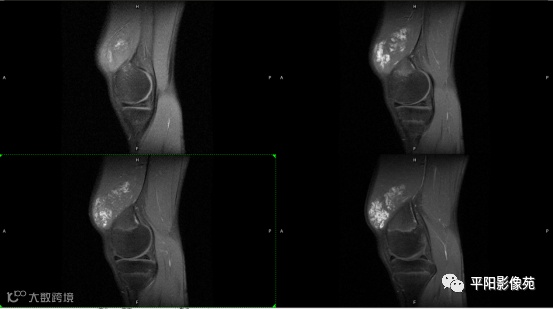

影像表现:

左膝关节股内侧肌内见多房样短T1长T2信号,内可见分隔,增强扫描明显强化,分隔未见明显强化,病灶局部与股骨远端分界不清。

MRI表现:好发于下肢, 较大病灶多为与肢体长轴一致的梭形, 边缘不清, 较小病灶呈类圆形, 边缘较清;②T1WI呈等或稍高信号, 病灶内部或边缘可见线条状或花边状高信号灶, 类似于皮下脂肪信号, T2WI上为明显高信号, 为本病特征性MRI表现;③病灶内静脉石及血管流空影为又一特征MRI表现;④GD-DTPA增强, 病灶明显强化, 其内低信号间隔无强化;⑤可见骨外形改变, 骨质增生及骨质吸收等表现。